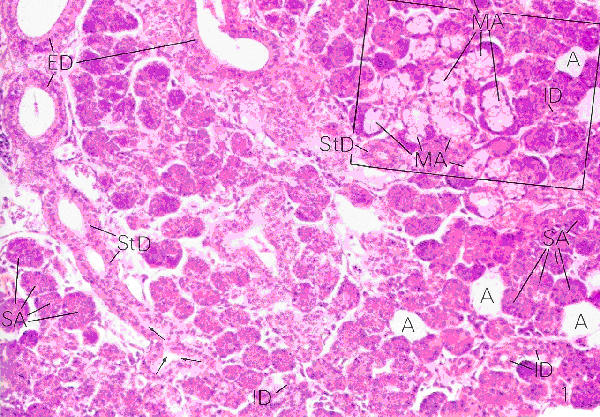

1.1 The Parotid gland

• Is surrounded by a dense connective tissue capsule

• Septae from the capsule divide the gland into lobules

• In the septae fat and lymphocytes are found

• The parotid is a compound tubulo-alveolar gland which is 100% serous

• It contains prominent intralobular secretory ducts

Plate 67 (Fig. 1)

Ross and Romrell p. 413

Secretory Ducts

Intralobular Duct

• Intra - inside the lobules

• There are two different intralobular secretory ducts

• The lumens of these ducts are prominent and their cytoplasm stain acidophilic

• The intralobular ducts originate in the lobules and continue as the interlobular ducts

• Intercalated ducts

• These ducts originate in the alveolus of the secretory units

• They consist of simple cuboidal epithelium that changes into simple squamous epithelium

• These ducts are well developed in the parotid, shorter in the submandibular and absent in the sublingual glands

• Striated ducts

• These ducts are the continuation of the intercalated ducts

• They are larger and lined with simple columnar epithelium

• The basal part of these cells have a striated appearance due to the intricate folding of the cell membrane

Interlobular Ducts

• Inter - between the lobules

• The interlobular ducts are found outside the lobules in the connective tissue septa

• The epithelium begins as simple cuboidal and changes to simple columnar and/or pseudostratified epithelium.

• Eventually the epithelium changes to the same epithelium that covers the surface at its opening into the oral cavity

• The interlobular ducts join to form the main secretory duct